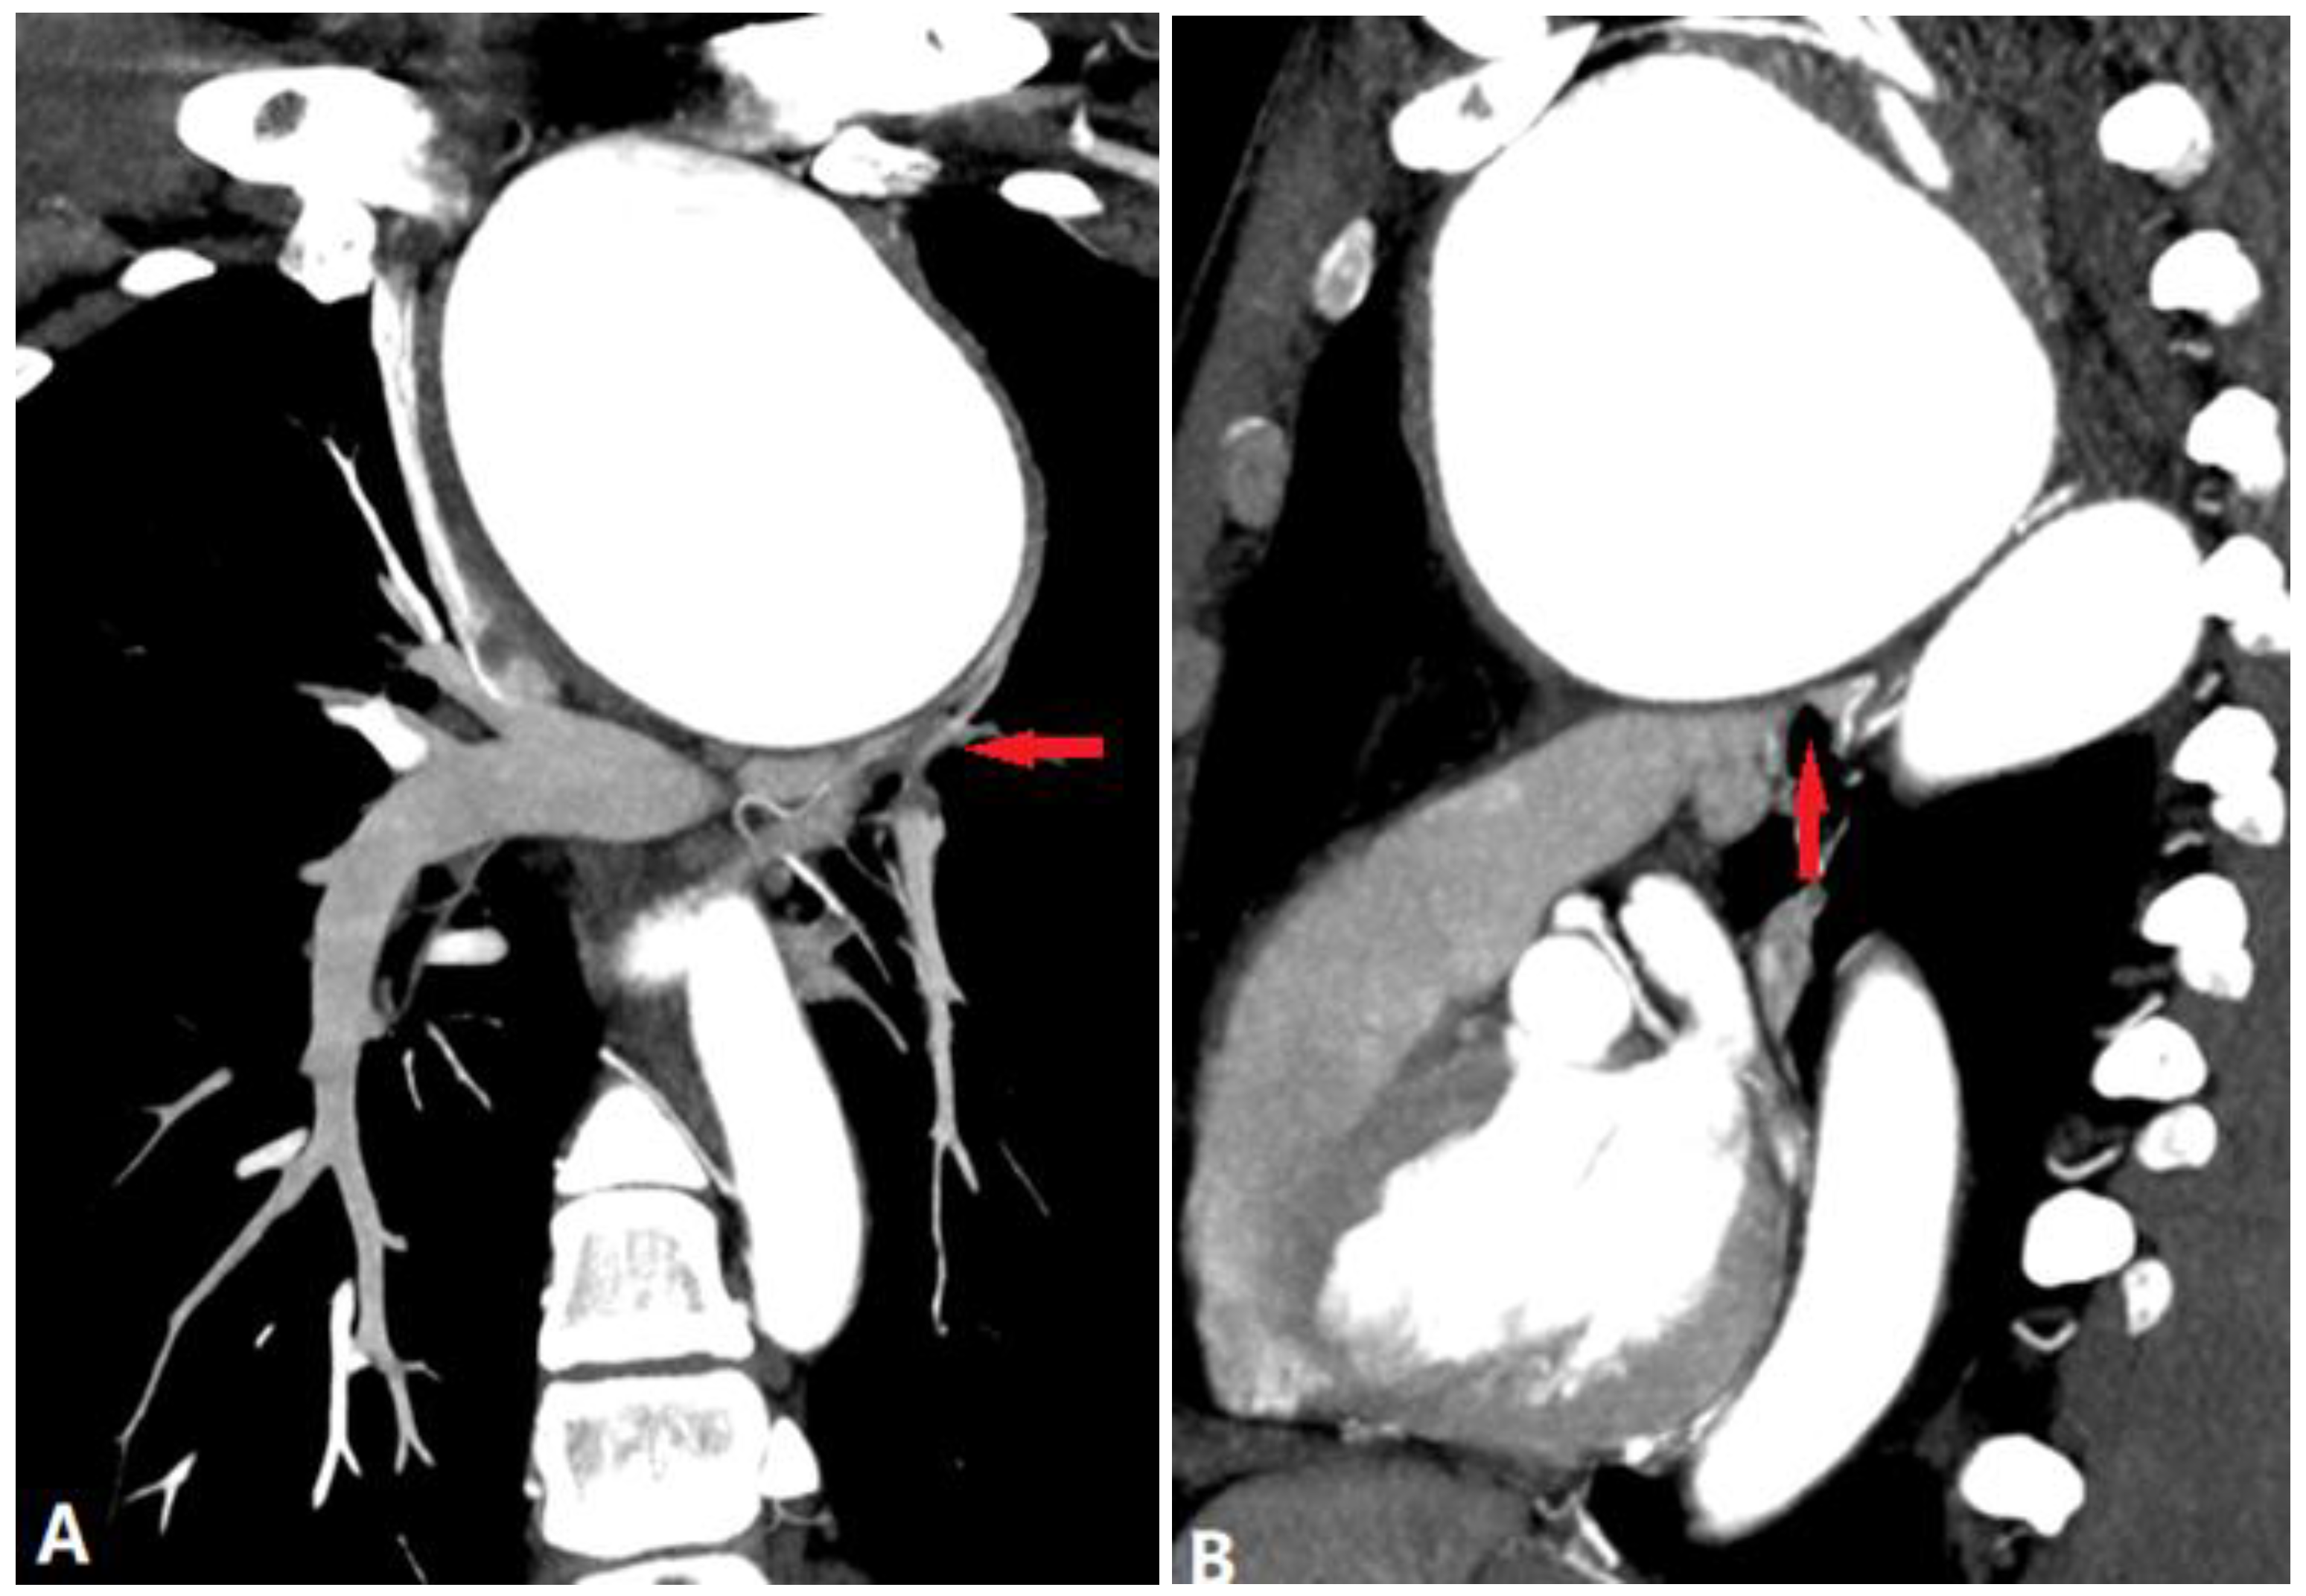

4.3.3. Aortic Aneurysm

5. Complications of Radiofrequency Ablation of Atrial Fibrillation